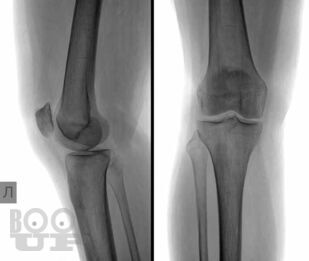

В основу книги положен многолетний опыт исследований коленного сустава в многопрофильной клинике с развитой ревматологической и ортопедической службами. Авторами приводится непредвзятое освещение возможностей современных методов лучевой диагностики патологии коленного сустава с адекватным позиционированием ультразвуковых исследований на различных этапах оказания медицинской помощи. Проанализирован опыт отечественных и зарубежных авторов, суммированы результаты многочисленных оригинальных собственных исследований. Подробно освещены особенности ультразвукового исследования широкого спектра патологических состояний и заболеваний травматического, воспалительного генеза, встречающихся у молодых и пожилых пациентов.

В книге представлен большой иллюстративный материал. Подробно изложена топографическая и ультразвуковая анатомия коленного сустава, рассмотрены технические особенности проведения исследования, варианты визуализации многочисленных патологических изменений.